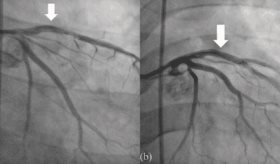

Joven puertorriqueño enfrenta infarto agudo con elevación del ST asociado síndrome antifosfolípido

El síndrome coronario agudo rara vez ocurre en individuos jóvenes y rara vez se asocia con el síndrome antifosfolípido.